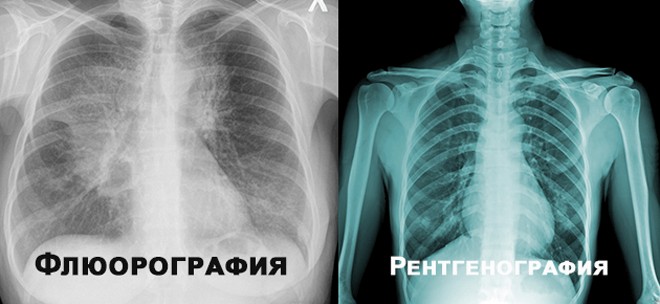

Но если уж какое-либо заболевание органов дыхательной системы возникло, то его необходимо лечить, причём начать лечение желательно с самых ранних стадий недуга. Для ранней диагностики заболеваний лёгких применяют флюорографию - фотографирование изображения грудной клетки, просвечиваемой рентгеновским излучением. Флюорографию нужно делать хотя бы раз в два года. Это позволяет выявить целый ряд опаснейших заболеваний на ранних стадиях.